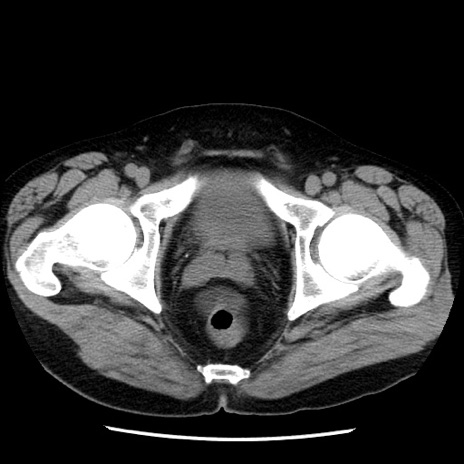

症例29(横断像)

【症例】40歳代男性

【現病歴】2日前から胃痛あり。徐々に周期的な激痛に変化した。本日になっても激痛があるため受診。

【身体所見】意識清明、BT 38-39℃台あり、腹部:膨満、やや硬、右下腹部に圧痛あり。

【データ】WBC 8500、CRP 23.26